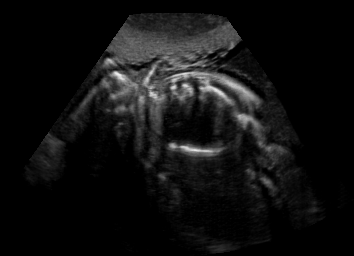

Real in-vivo images. 22 ultrasound sequences were collected using a GE Voluson E8 machine during standard fetal screening exams of 8 patients. Each sequence is several seconds long. We extracted all 4427 frames and resize them to , see Fig. 2 for some examples. The resulting image set was randomly split into training-validation-test sets by a 80-10-10% ratio.